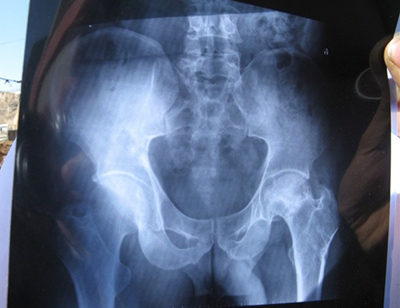

此時去醫院體檢做檢查時,X線表現為股骨頭外形正常,只有一些軟骨下出現囊性變或者新月征。這個時候的骨小梁結構排列已經紊亂或者斷裂,股骨頭的邊緣也出現毛糙的現象。如不仔細發現,易忽視病情。

此時,X線依舊沒有表現出股骨頭壞死的明顯征兆,患者會感覺到疼痛變得明顯,活動受到輕微的限制。患者開始引起注意。

骨壞死期。股骨頭的形態改變,頭部出現階梯狀塌陷或者出現雙峰征,軟骨下有細微骨折線,出現邊緣不完整、蟲蝕狀、扁平等形狀,骨小梁的部分結構也消失了,負重區域明顯變扁,骨密度明顯出現很不均勻的狀況,出現骨質疏松的癥狀。

致殘期。這個時候X片會看到股骨頭扁平、增大、關節間隙狹窄或者消失、囊狀改變明顯,股骨頭出現大面積不規則塌陷或變平,骨小梁結構變異。骨質硬化面積變大,股骨頭軟骨明顯斷裂,關節面粗糙。